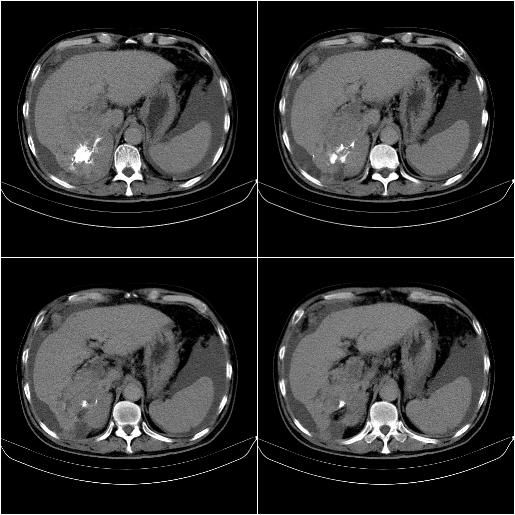

标题: CT21651:M,67Y,肝癌9月,介入术后3月。

m,67y,肝癌9月,介入术后3月。现腹胀、纳差、腹泻。

1)肝癌介入治疗术后碘油沉积不良。2)门静脉瘤栓形成,腹膜广泛性转移。3)肝硬化,脾大,腹水。4)慢性胆囊炎。